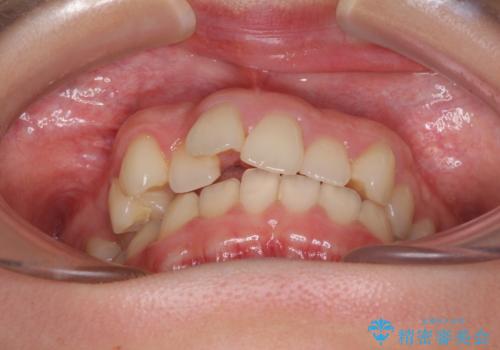

- 上顎前歯のデコボコを気にして来院された患者様です。

口元の突出感はなく、上顎のみに顕著な叢生が認められました。

上顎の左右第一小臼歯2本を抜歯し、ワイヤー装置にて歯列を整えることとしました。